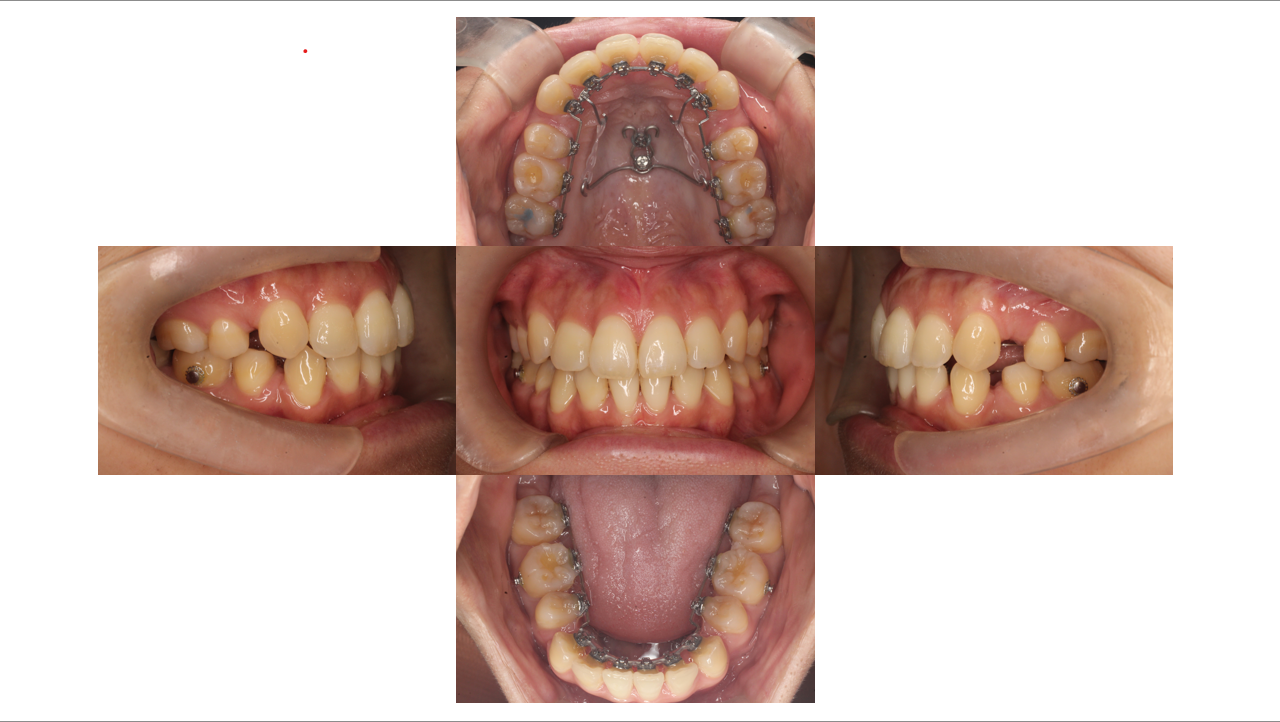

Before

叢生改善・出っ歯改善・裏側(リンガル)矯正